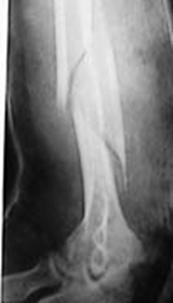

Fractura de humerus

Sindrom de compartiment Sindrom de compartimen

Fasciotomie mediala superficiala Fasciotomie mediala

Sindrom de compartiment Plaga impuscata in regiunea poplitee

Fasciotomie laterala